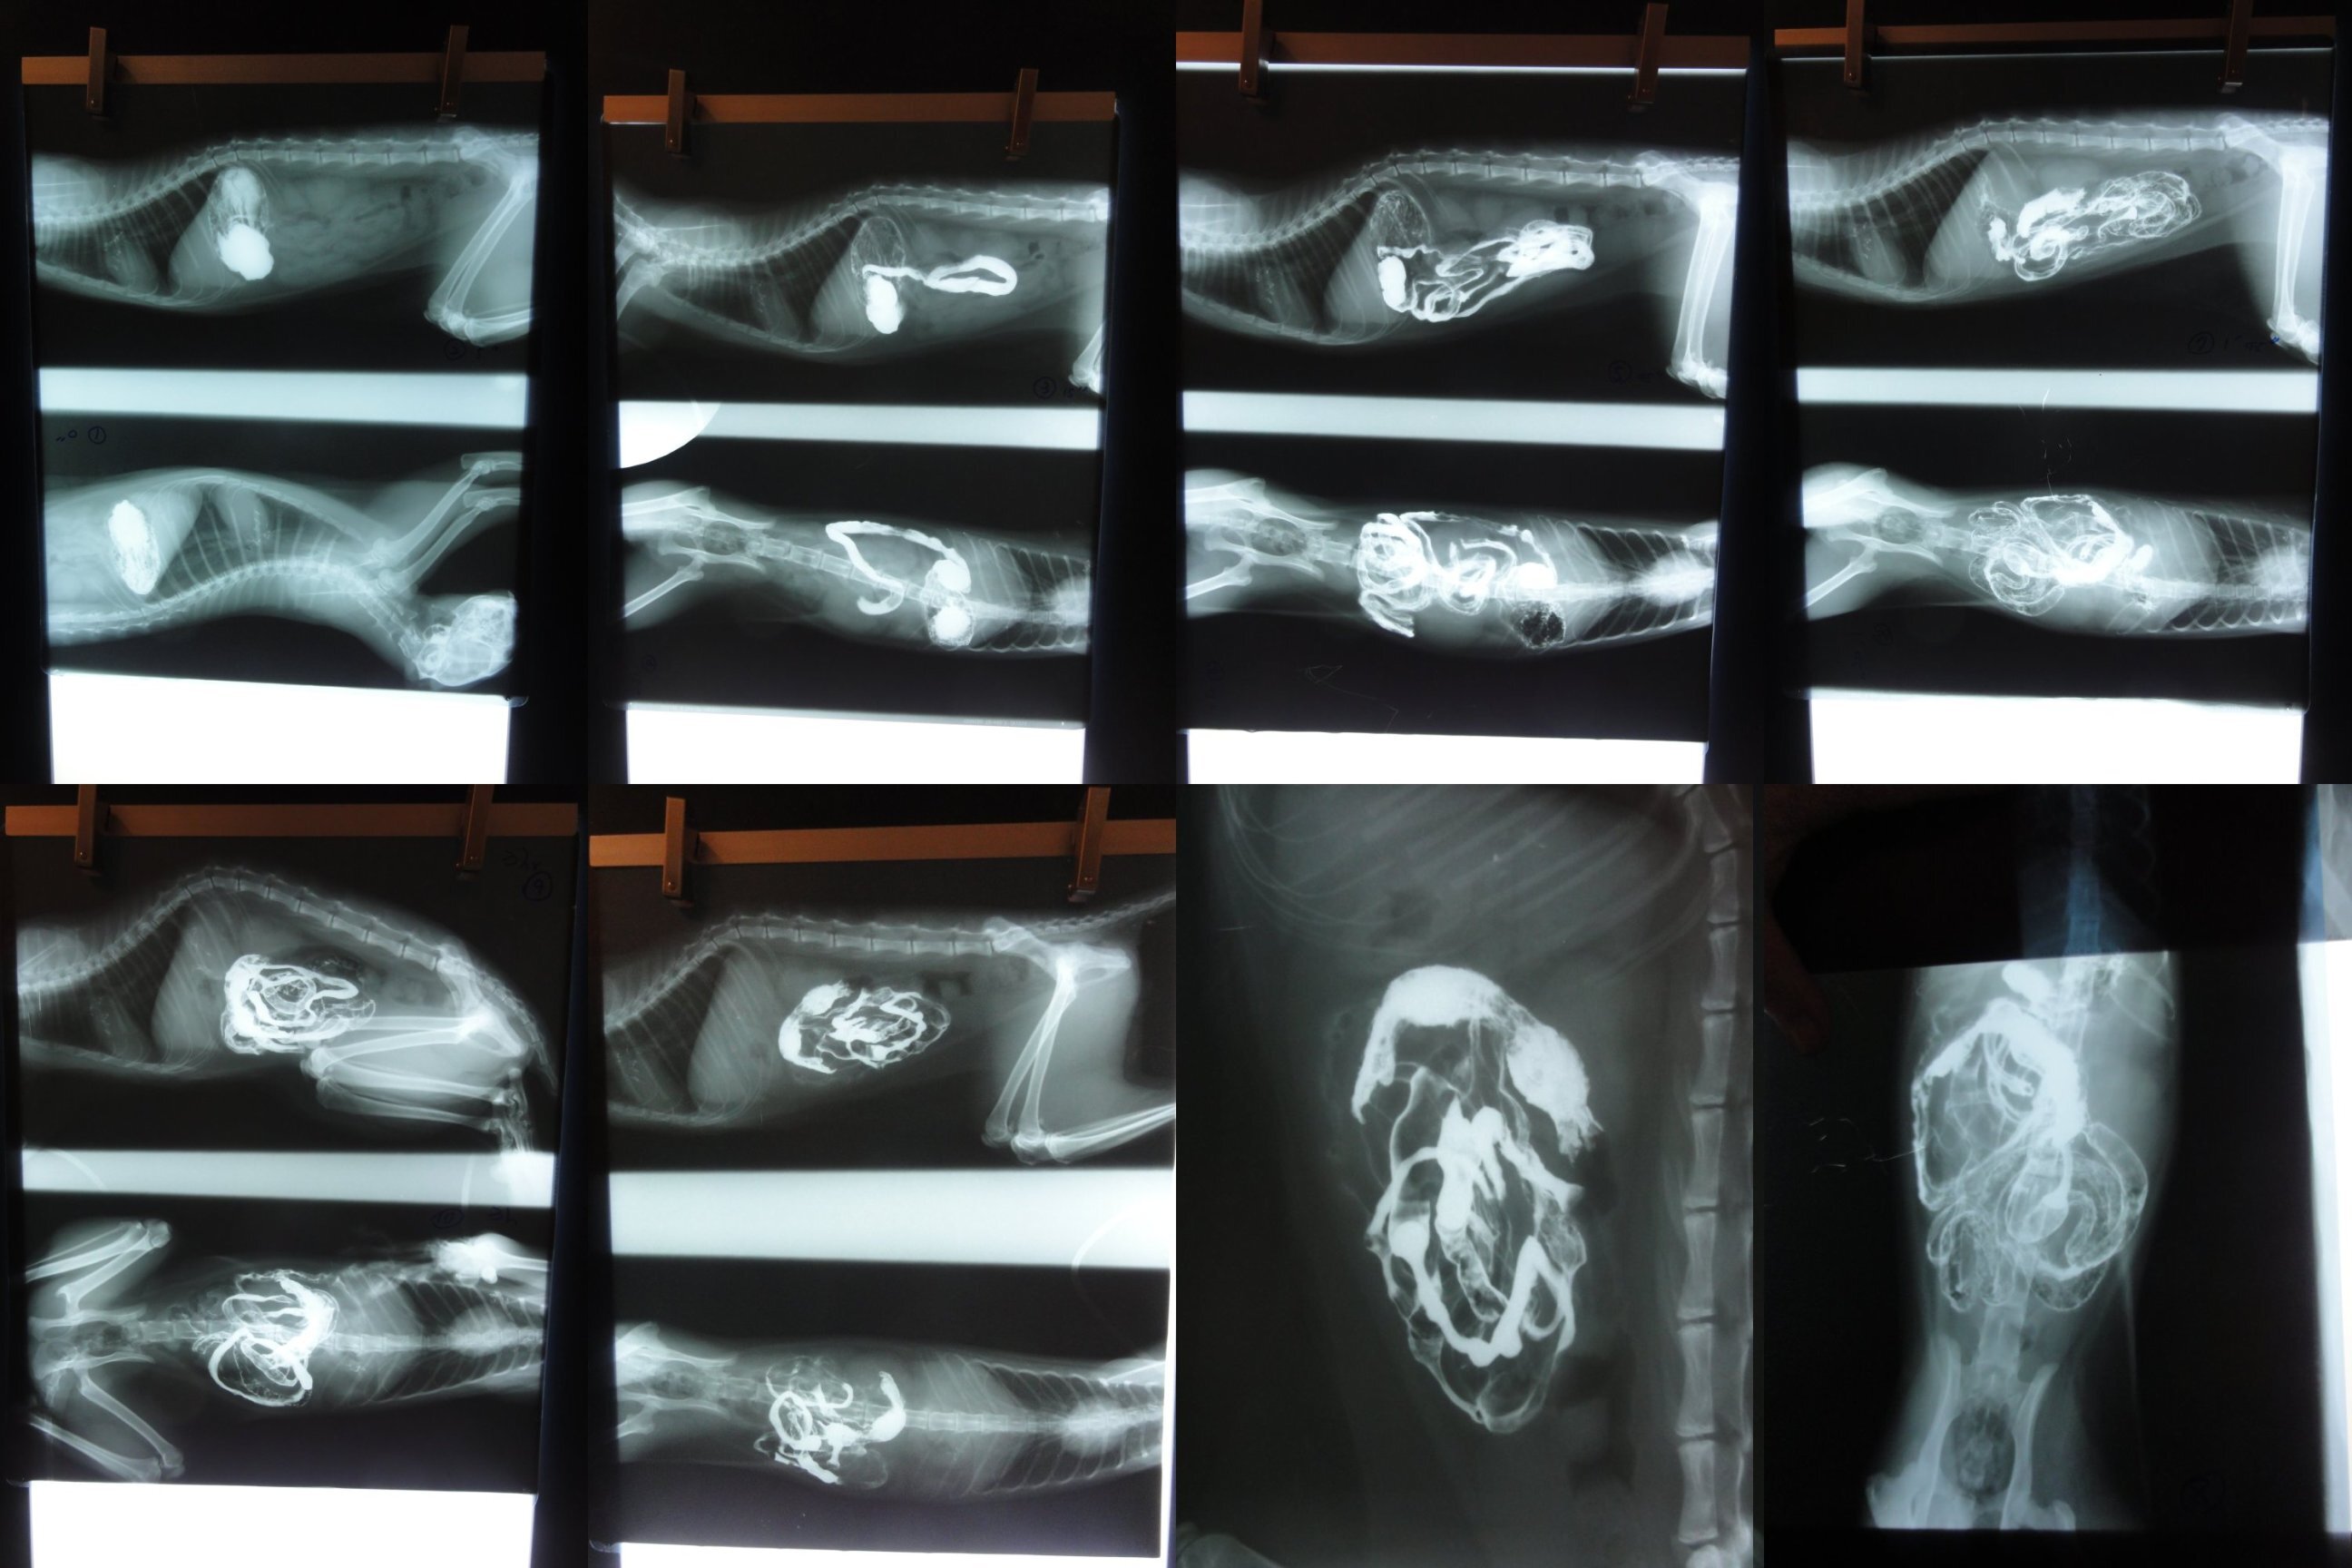

經過X光造影發現,腸內有異物阻塞,應是無法進食及嘔吐主因,經手術後取出類似粘土的不明物體,阻塞在腸內,原以為手術後應會很快恢復健康,但貓還是每天躺著,且有呼吸道感染,需做噴霧治療,無法自行進食,需以人工餵食,但可以明顯發現貓展現出他想進食的本能,只是無法自己起身吃東西,而進食後的嘔吐現象也沒有了,這期間做了血液檢查、細菌培養等,都呈現正常反應,但貓卻像一點力氣也沒有般的只能躺著,經過投以肌力無力症葯物,還是不見效果,貓最後因腦性麻痺導致全身肌肉無力,最後呼吸肌肉衰竭而離世。